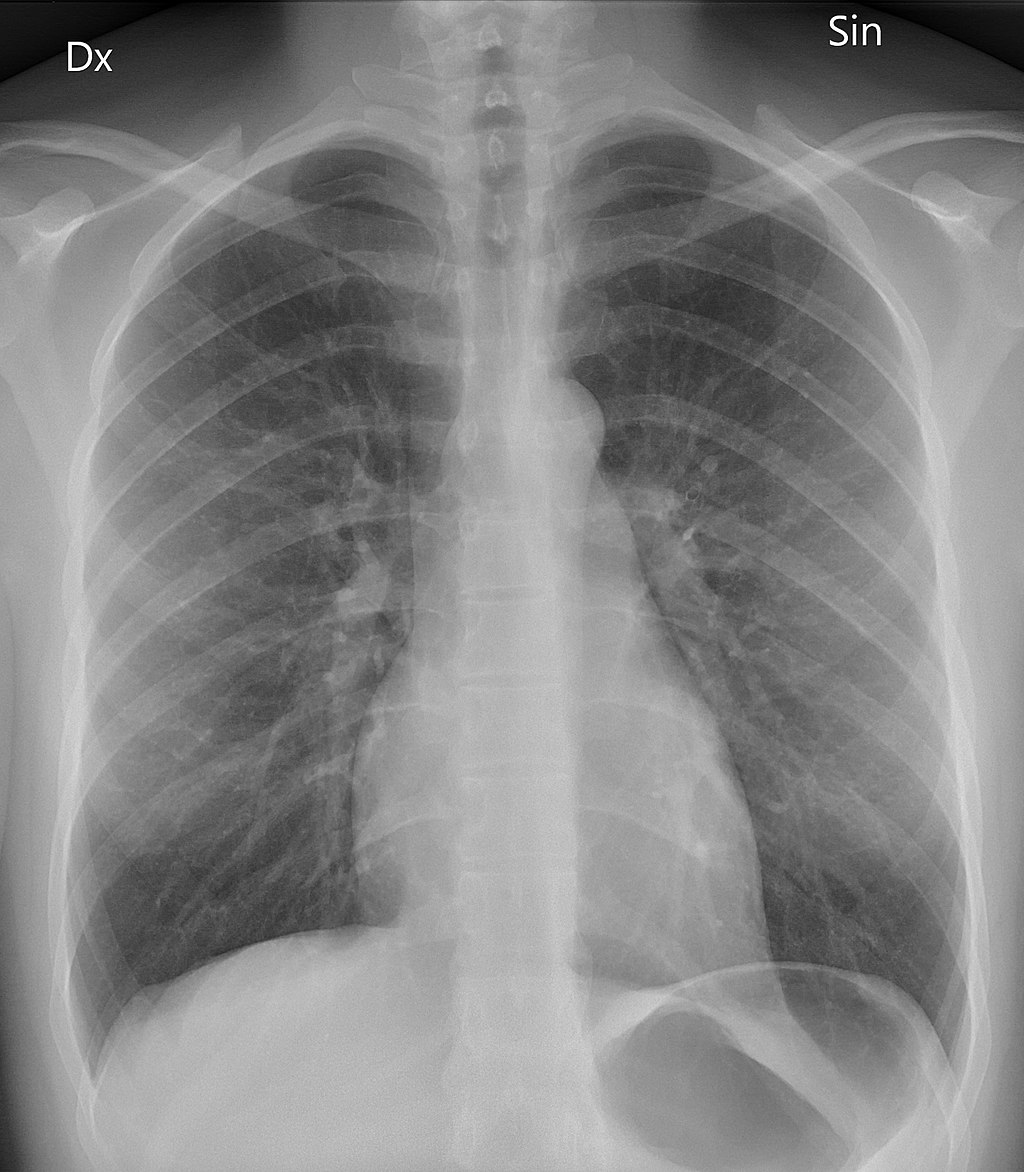

So if you are presented with a CXR like this, let’s see how to go through it.

Now that we know how to systematically go through a CXR, let’s have a look at how we would interpret the CXR we saw at the beginning.

CXR Interpretation

D – This is a Chest X-Ray taken on ….., of the following patient….. Is there a previous CXR to compare to

R – Commenting first on the quality, it is not rotated, there is adequate inspiration, the projection is posterior-anterior and it is adequately exposed as I can see the vertebral bodies clearly

On initial inspection, there is no obvious pathology, but I will proceed to go through it systematically.

A – Starting with the airways, the trachea is not deviated, and the carina is visible.

B – The pleural markings go all the way to the costal margin so there is no evidence of a pneumothorax. Going through the lung zones, there is no area of increased opacification and both hila appear normal.

C – The heart is not enlarged and the borders are clearly visible.

D – The hemidiaphragms are clearly visible and there is no blunting of the costophrenic angles. There is no free air under the diaphragm.

E – There are no foreign objects or bone fractures.

There is no abnormality in the review areas, including the apices, behind the lung

In summary this is a normal chest X-Ray